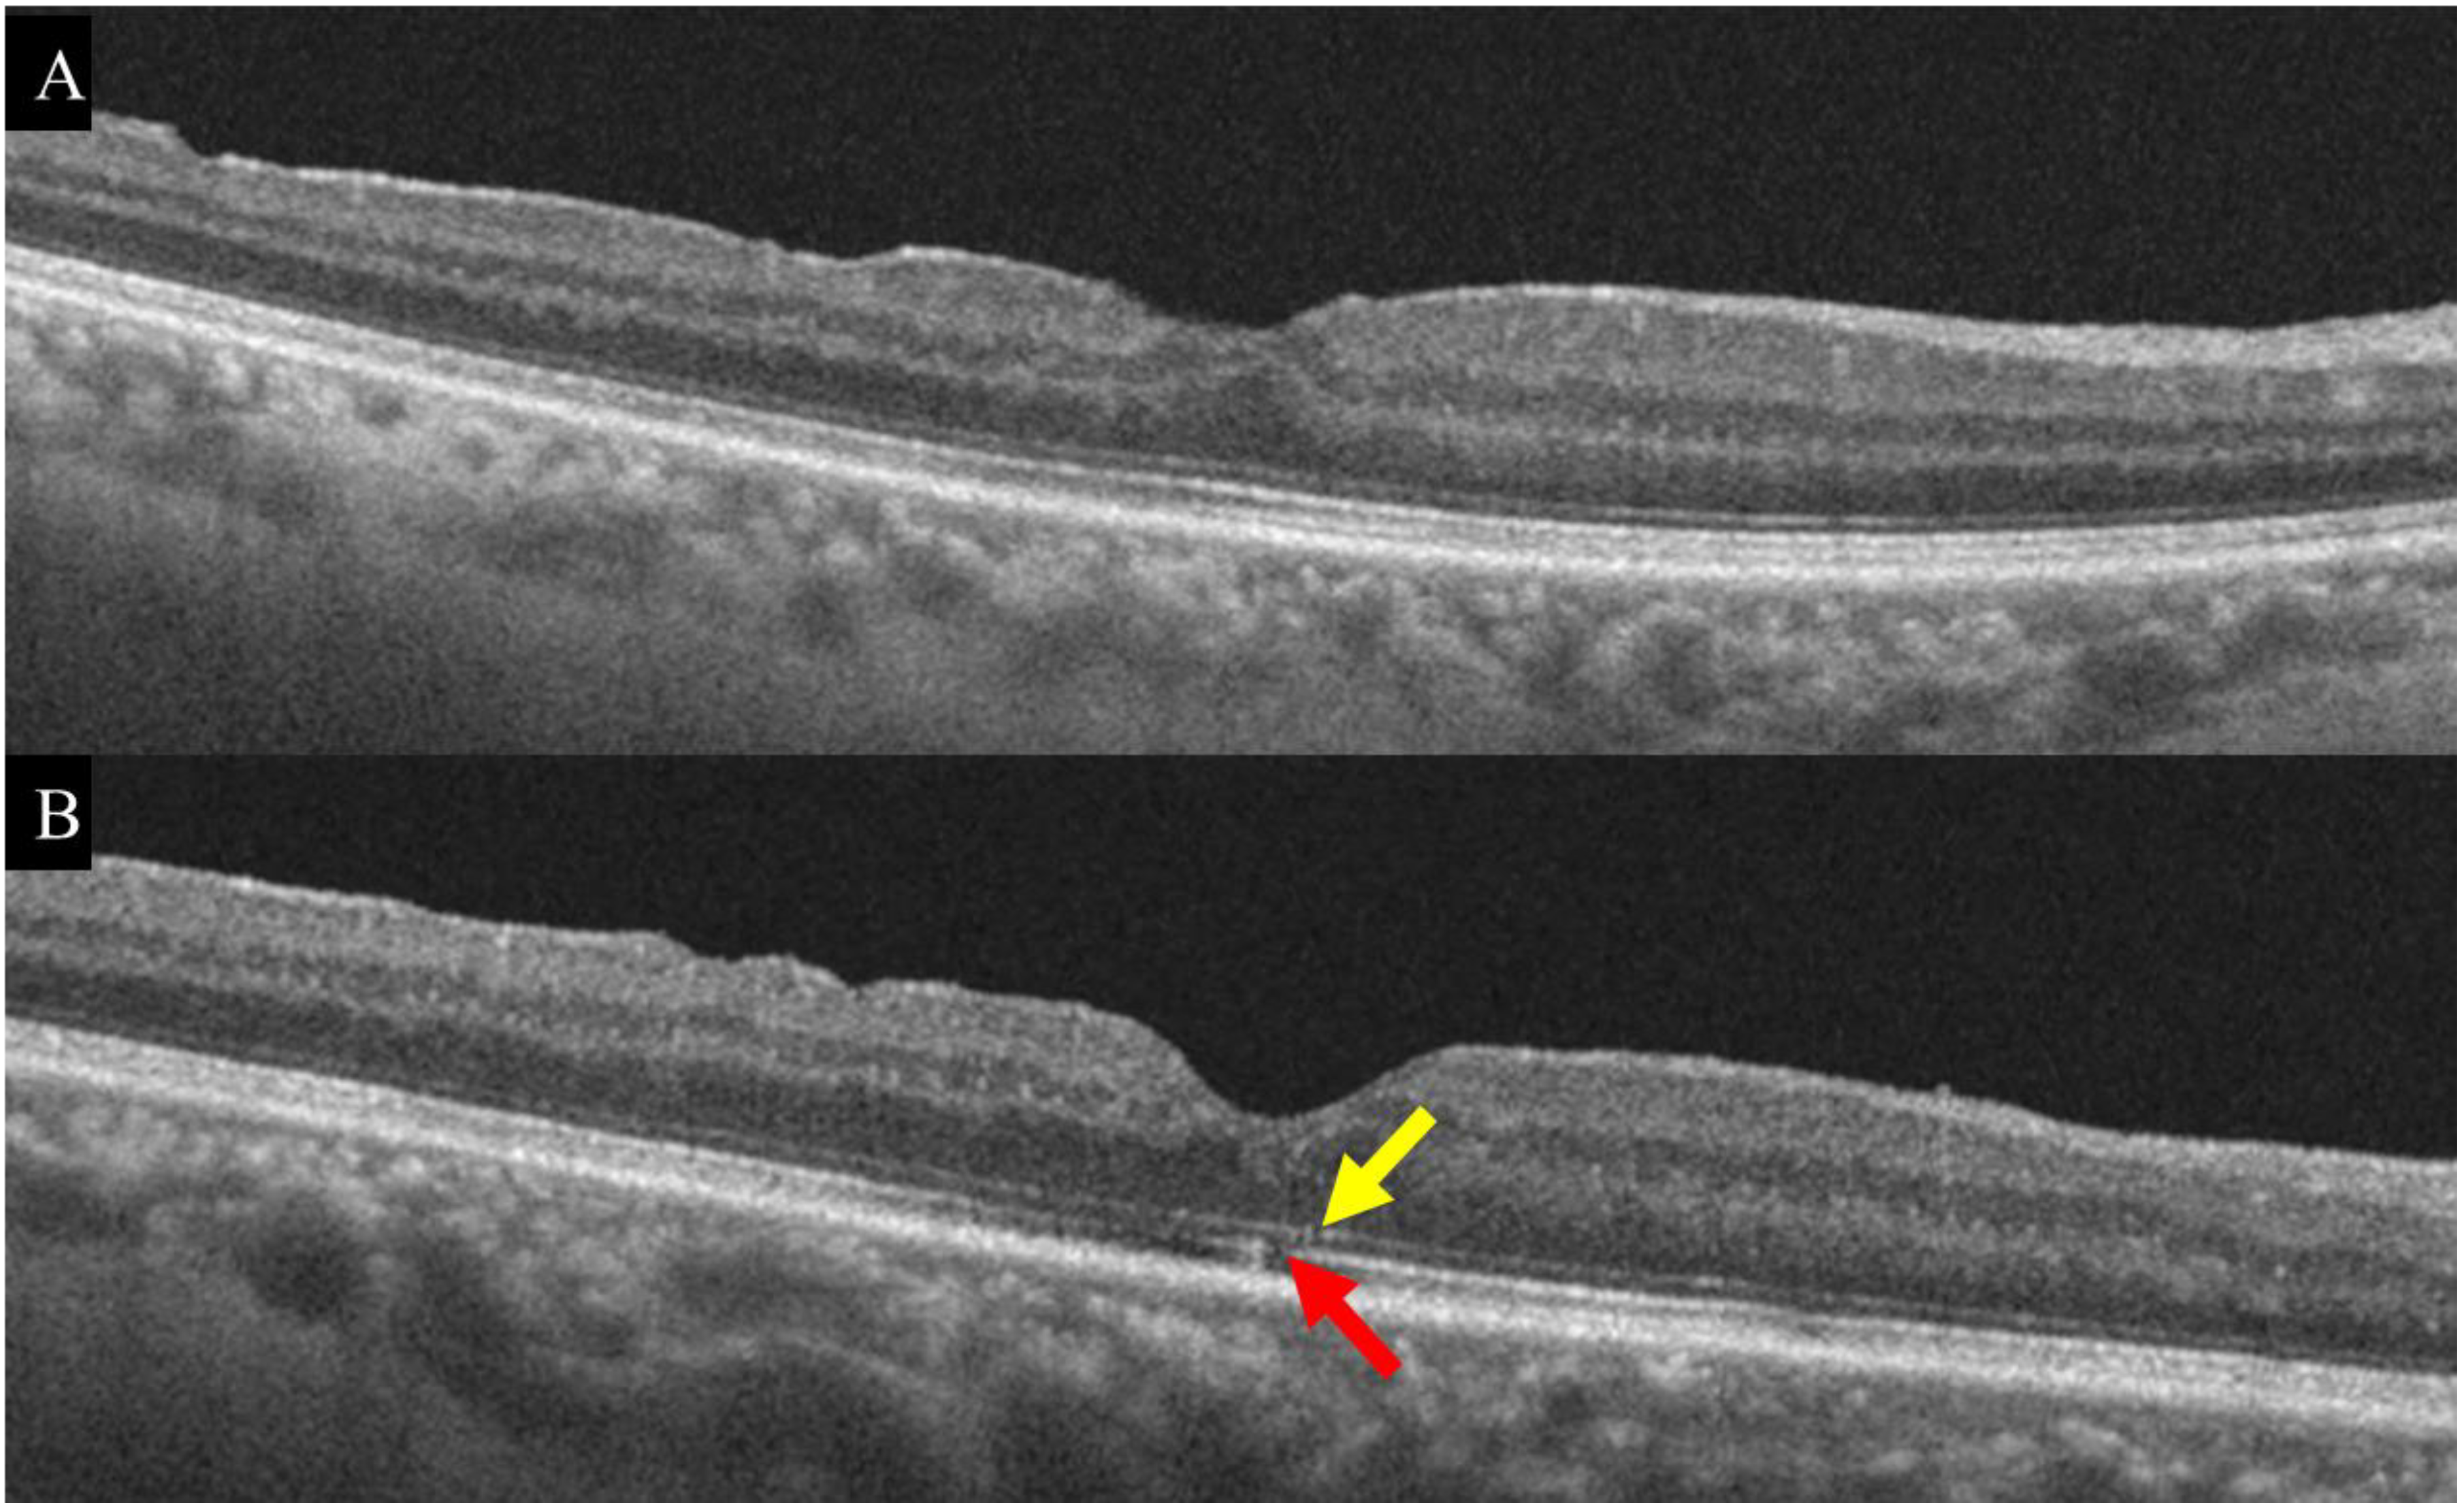

3.2. Changes in OCT and OCTA Parameters after MH Surgery